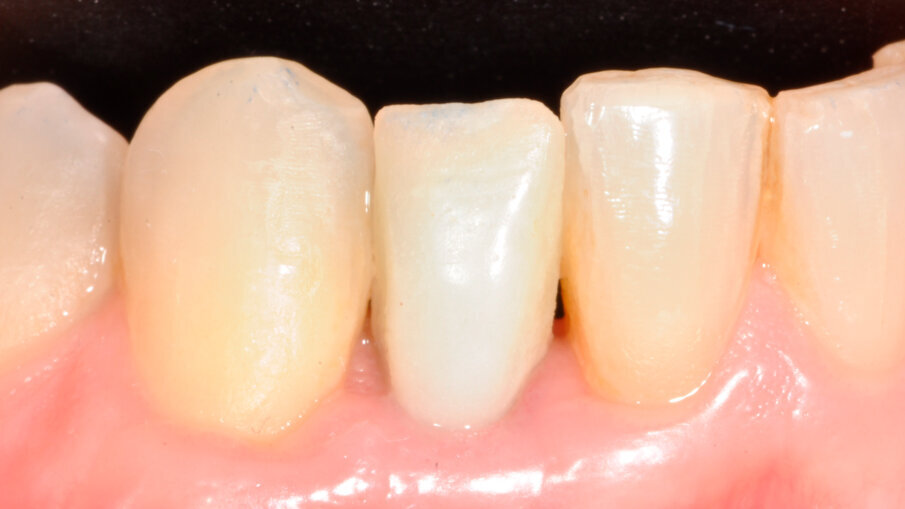

40letý pacient s chybějícím pravým postranním řezákem v dolní čelisti a štěpem transplantovaným do oblasti tohoto chybějícího zubu požádal o rekonstrukci za použití dentálního implantátu. U tohoto typu náhrady je problémem omezený dostupný prostor a blízkost sousedních zubů. Při klinickém vyšetření byl posouzen dostupný prostor (obr. 1) a na periapikálním RTG snímku pořízeném před ošetřením byla vyhodnocena oblast pro zavedení implantátu (obr. 2). Plán ošetření zahrnoval konvenční zavedení implantátu za použití implantátu OsseoSpeed EV (Dentsply Sirona) a bezprostředně po zavedení implantátu byla nasazena provizorní náhrada na abutmentu Temporary Abutment EV (Dentsply Sirona). Pro definitivní náhradu bylo naplánováno použít za účelem obnovy přirozeného vzhledu a funkce chybějícího zubu korunku na abutmentu Atlantis Crown Abutment (Dentsply Sirona).